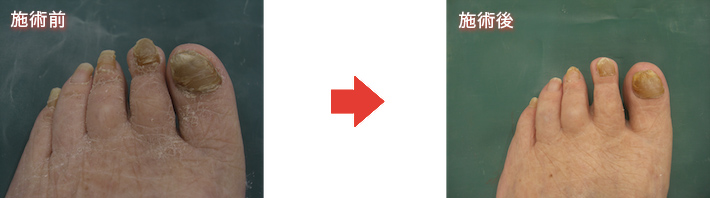

フットケア

足は一日中、体重を支えて歩き回るため、非常に疲れやすい部位です。それなのに足の手入れはおろそかになっていないでしょうか。

巻き爪、陥入爪などの爪のトラブル、胼胝(たこ)、鶏眼(うおのめ)、足のむくみ、痛みなど、足のトラブルに悩まされている方が急増しています。

困っているけどどこに行けばいいのか分からず、そのままになっている方が多いのです。

当院では、足病変の予防、早期治療につながるよう、肥厚爪、陥入爪、巻き爪、胼胝(たこ)、鶏眼(うおのめ)の処置を実施しております。

ご自身で足の爪が切れなくなった、爪が厚くなって爪切りでは切れないなどでお困りの方はお気軽にご相談ください。

爪切り(医療用、専用の機器で処置)

・・・肥厚爪 10~15分程度

保険診療(3割負担 180円)

胼胝(たこ)、鶏眼(うおのめ)の処置(専用の機器で処置)

・・・10分程度

保険診療(3割負担 510円)

巻き爪(クリップ)

5,000円

巻き爪(ワイヤー)

10,000円 2回目以降 2,100円